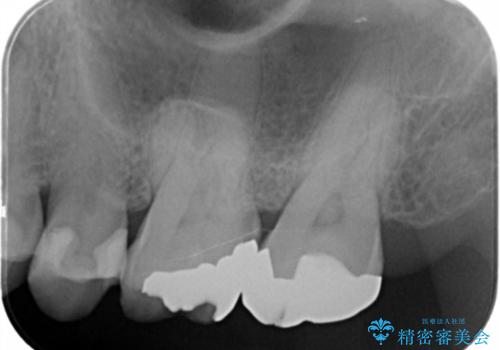

- 口の中に見える銀歯を、金属アレルギーの対策と審美性の向上のため全て除去したい!と希望され来院されました。

銀歯を丁寧に除去したのち、精度の良いセラミックインレー、セラミッククラウンで修復・補綴処置を行っていきます。

- 62.7万円(ジルコニアクラウン×3・仮歯×3・セラミックインレー×3)費用は治療当時の料金となります